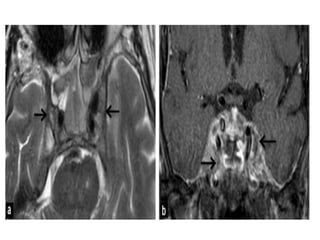

• #35 Schwannoma of the trigeminal nerve (T1-weighted sequences and T2).

Trigeminal schwannomas typicallyfollow the course of the fifth cranial nerve and have a dumbbell-shaped configuration. They are smoothly marginated tumors and are usually isointense comparing to gray matter on T1WI and hyperintense on T2WI. Small tumors are homogeneous; large tumors can have heterogeneous signal intensity due to degenerative changes, including cyst formation and fatty degeneration.

MRI Schwannomas have fairlypredictable signal characteristics: •T1: isointense or hypointense •T1 C+ (Gd): intense enhancement •T2: heterogeneously hyperintense cystic degenerative areas may be present, especially in larger tumours •T2*: larger tumours often have areas of haemosiderin Several signs can also be useful: •Split-fat sign: the thin peripheral rim of fat best seen on planes along the long axis of the lesion in non-fat-suppressed sequences. •Target sign • peripheral high T2 signal. • central low signal. • rarely seen intracranially. •Fascicular sign: multiple small ring-like structures.

Schwannoma of theMeckel´s cave.